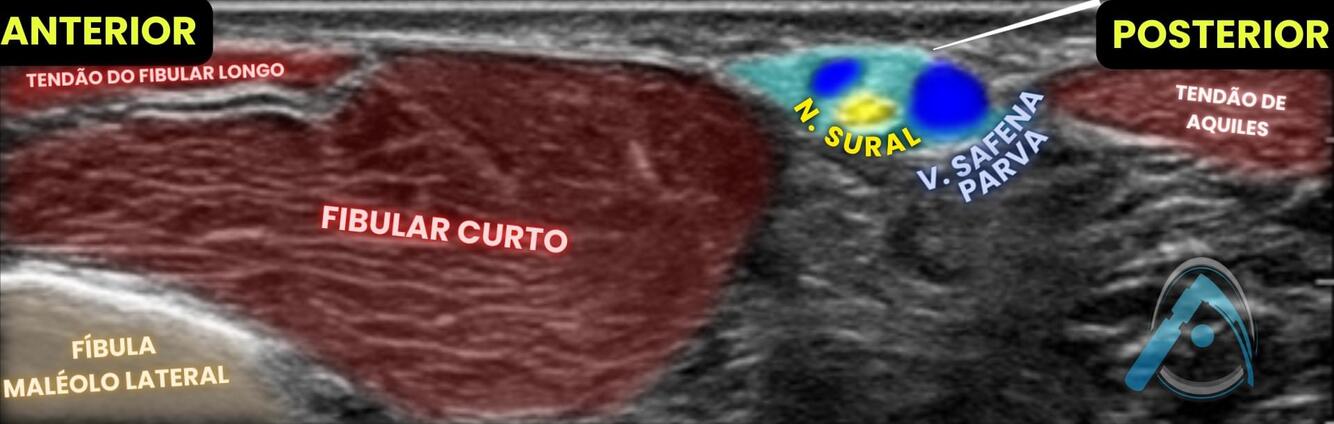

No bloqueio abaixo para uma cirurgia de pé, o que são as estruturas apontadas?

A

1 - nervo fibular;

2 - tendão de aquiles;

3 - fibular longo

Esse é o bloqueio do nervo sural.